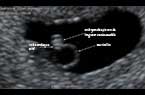

Embryon de 6 SA et jours : cmpositions du sac gestationnel Embryon de 6 SA et jours : cmpositions du sac gestationnel Embryon de 6 SA et jours : cmpositions du sac gestationnel